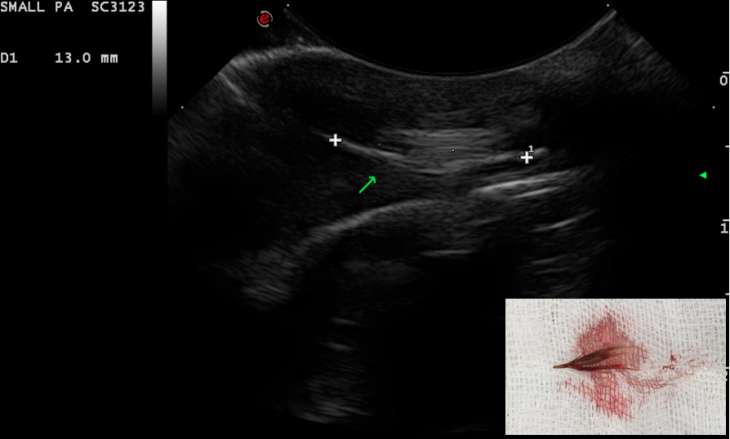

The use of ultrasound for the detection of such foreign bodies is well known and their ultrasonographic features have been widely discussed. Grass awns ‘appear as linear spindle-shaped hyperechoic structures of variable length, with two or three parallel reflecting interfaces corresponding to the seeds and seed covers. Often an anechoic halo due to the accumulation of fluid is present around the foreign body, which sometimes improves interface visualisation’.

Four dogs referred for recurrent abscess in the lumbar region have been seen at the hospital between October 2018 to January 2019. A migrating vegetal foreign body was identified in each dog with the use of ultrasonography. All retrieval procedures were performed in the sonography suite with the patient under general anaesthesia. The region of interest was aseptically prepared and a small stab incision with a #11 scalpel was performed approx. 2 cm cranial to the foreign body, with the plant awn imaged in sagittal section. A Hartmann forceps was inserted through the skin incision and directed toward the tip of the foreign body under ultrasonographic guidance. The forceps were opened and the foreign body grasped and withdrawn. The shape of the foreign body was compared with the sonographic images and the site of the abscess was re-scanned to determine potential residual foreign bodies or fragments. In all dogs, the abscess was flushed with saline and oral antibiotic therapy was administered for 7–10 days. The duration of the procedure ranged from 20 to 40 minutes. Suture of the skin incision was not necessary.